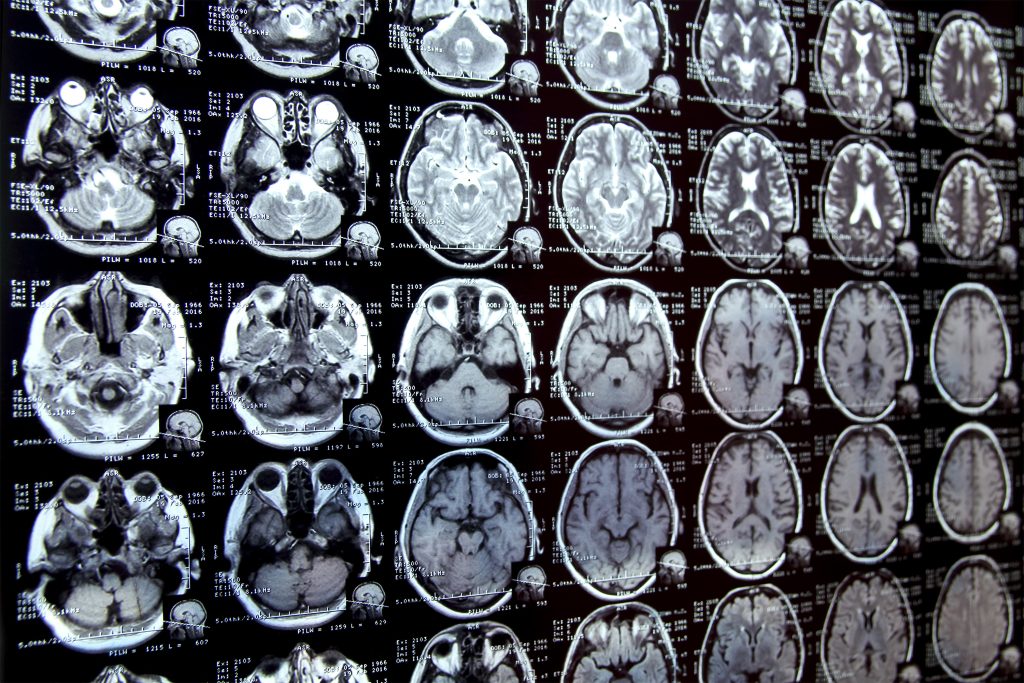

Medical image segmentation is a critical step in clinical research, providing insights into various aspects of patient health. This process involves annotating regions of interest in biomedical images, which can be time-consuming and labor-intensive, especially for complex structures like the brain’s hippocampus. Researchers at MIT have developed an AI-driven solution, MultiverSeg, that significantly streamlines this process by allowing users to interact with images in a more intuitive way.

In clinical studies, analyzing how organs or structures change over time often requires precise delineation of those areas in imaging scans. For instance, studying how the hippocampus alters with age involves circling the hippocampus in multiple scans. Traditionally, researchers manually perform this labor-intensive task, which can limit the number of images they can process in a day. Such inefficiencies often hinder scientific exploration and delay advancements in medical treatments.